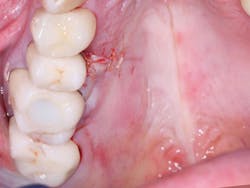

Figure 7: This shows severe postoperative pain caused by removal of large lingual periapical infection on first molar.

Figure 8: Closed wound of patient in Figure 7 healed rapidly with diminishing pain after 24 hours.